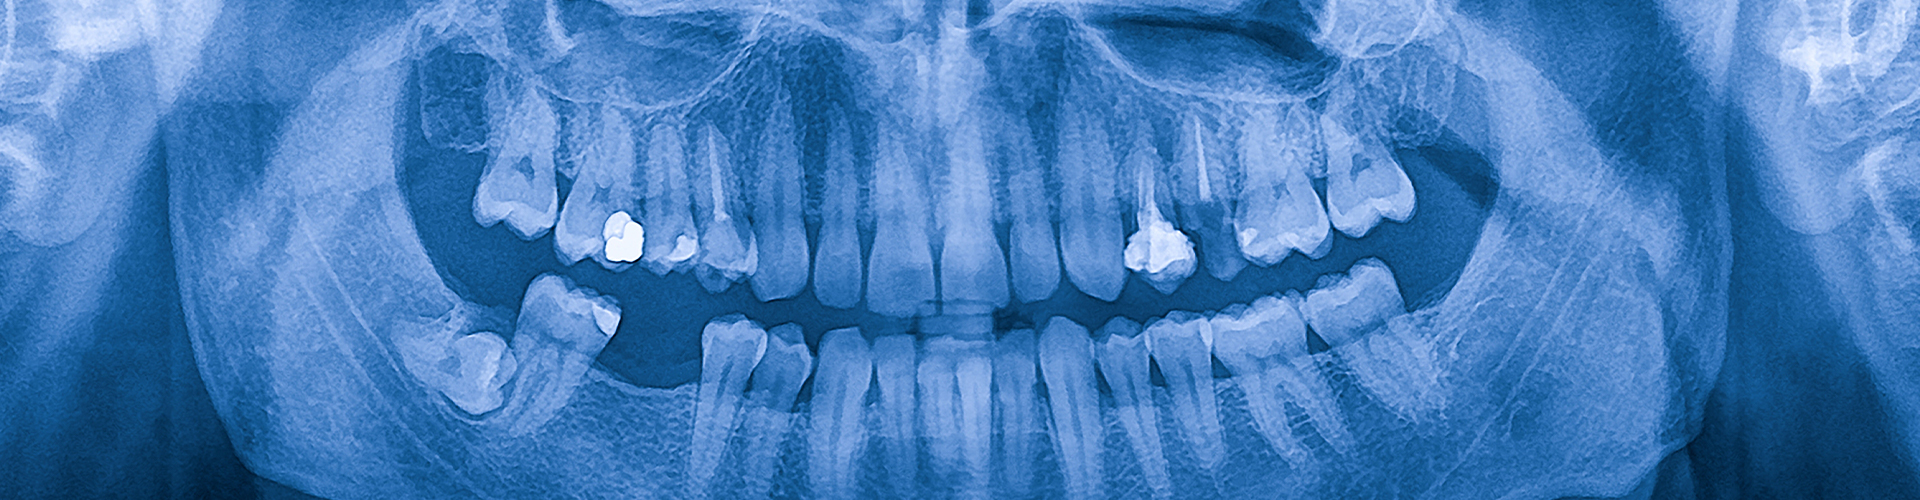

Wisdom teeth, or third molars, typically emerge in your late teens or early twenties. While some people’s wisdom teeth grow in without issues, others may experience complications due to limited space in the jaw.

These teeth can become impacted (trapped below the gums or angled improperly), causing pain, infection, or damage to surrounding teeth. Removing them can prevent or resolve these issues and protect your long-term oral health.

Wisdom teeth typically start developing between the ages of 17 and 25. During this time, we can monitor their growth with regular exams and imaging to identify any concerns early.

We can use X-rays and imaging to determine whether your wisdom teeth are problematic and advise you on the best course of action. Our team will also guide you through preparation, which may include: